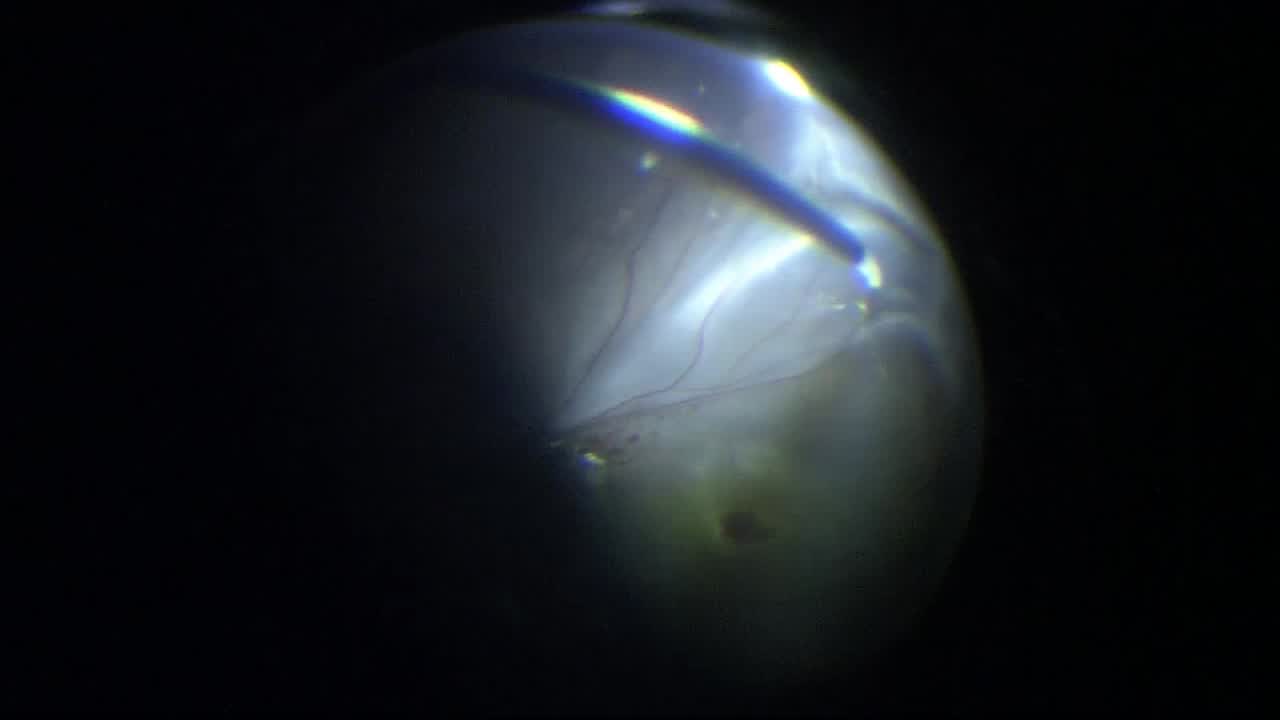

Retinal Detachment

Kazuaki Kadonosono, MD